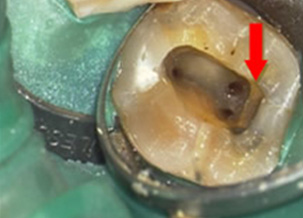

移除鈣化物後找到消失的根管

治療前